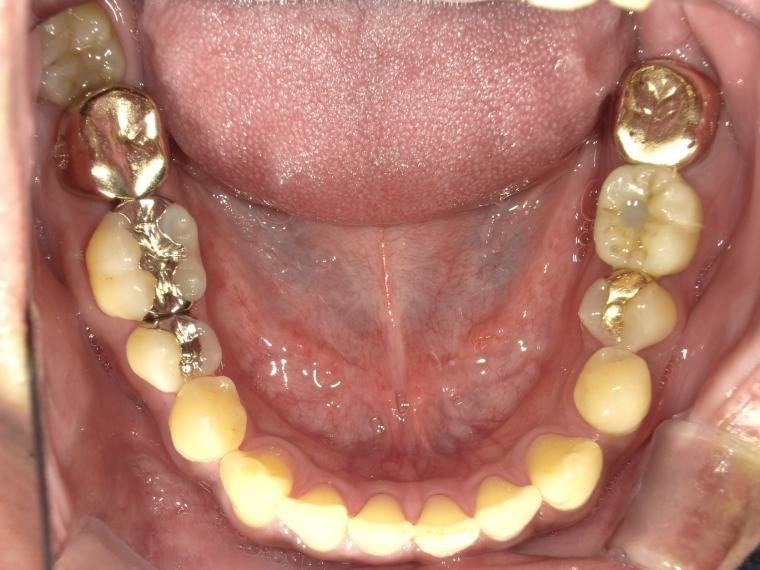

BEFORE

44歳男性

/下顎1本欠損/インプラント埋込手術

他院で左下第一大臼歯を治療していましたが、治療を中断してしまい、状態が悪化、抜歯になった患者さんです。